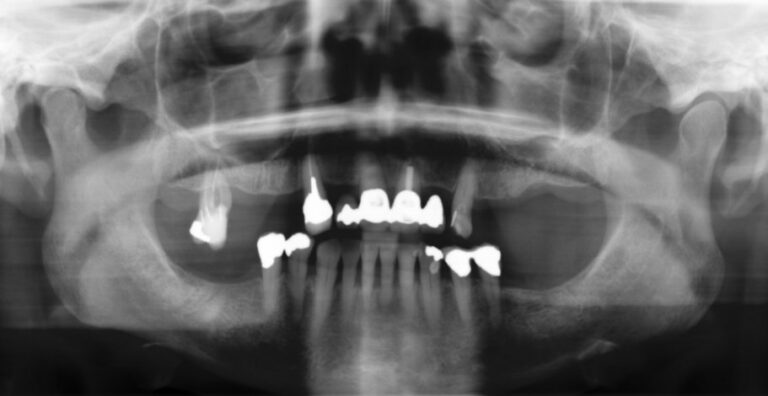

The most common cause of partial tooth loss is failing crowns or bridges. The natural roots are then too weak to support a bridge, and have to be extracted. We would usually extract the failing roots, place implants directly into their sockets, and place a fixed bridge immediately afterwards.